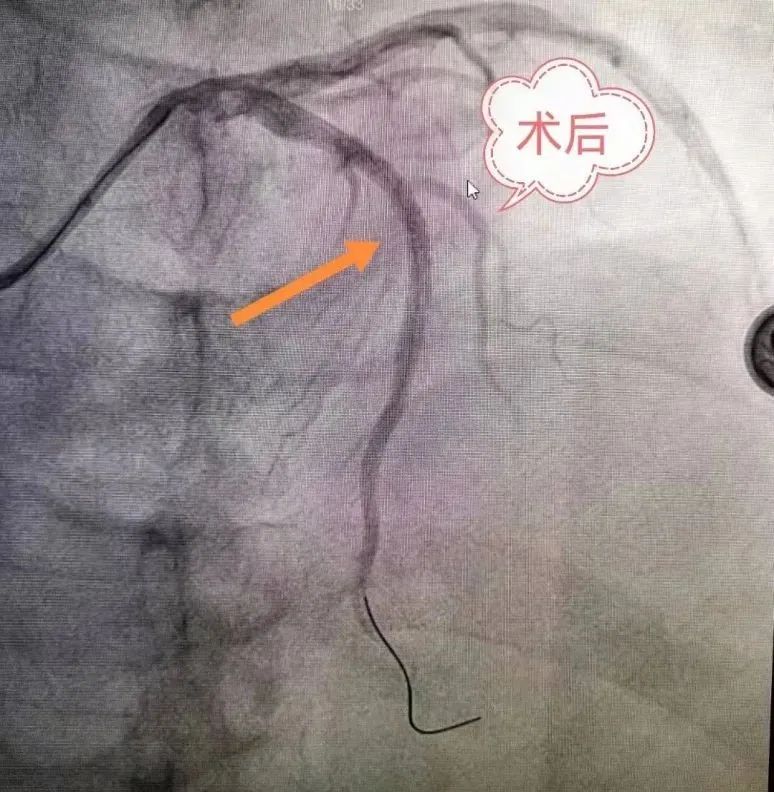

冠脉支架植入术是一种机械性的介入治疗手段,是处理急性冠状动脉闭塞最有效的手段,主要适用于急性心肌梗死、冠状动脉重度狭窄的病人;它是将药物洗脱金属支架永久性地置放于冠状动脉病变处,经球囊扩张释放或自膨胀方式支撑住血管壁,以保持冠状动脉管腔的开放,减轻局部心肌的坏死,降低急性心肌梗死的死亡率。

在DSA开机启用的背景下,我院介入导管室的成立填补了心内科、神经內科、神经外科等多学科介入治疗的空白,提升了我院综合救治能力,真正打造救命的“高速公路”。介入导管室成立至今,共开展冠脉动脉造影术、冠状动脉内支架置入术168台,经股动脉插管全脑动脉造影术8台,手术总费用达80万余。科学有效的护理干预是保障手术顺利进行的重要策略,追求严格的护理操作和耐心细致的心理疏导,为广大患者提供方便、快捷、高效的优质护理服务。